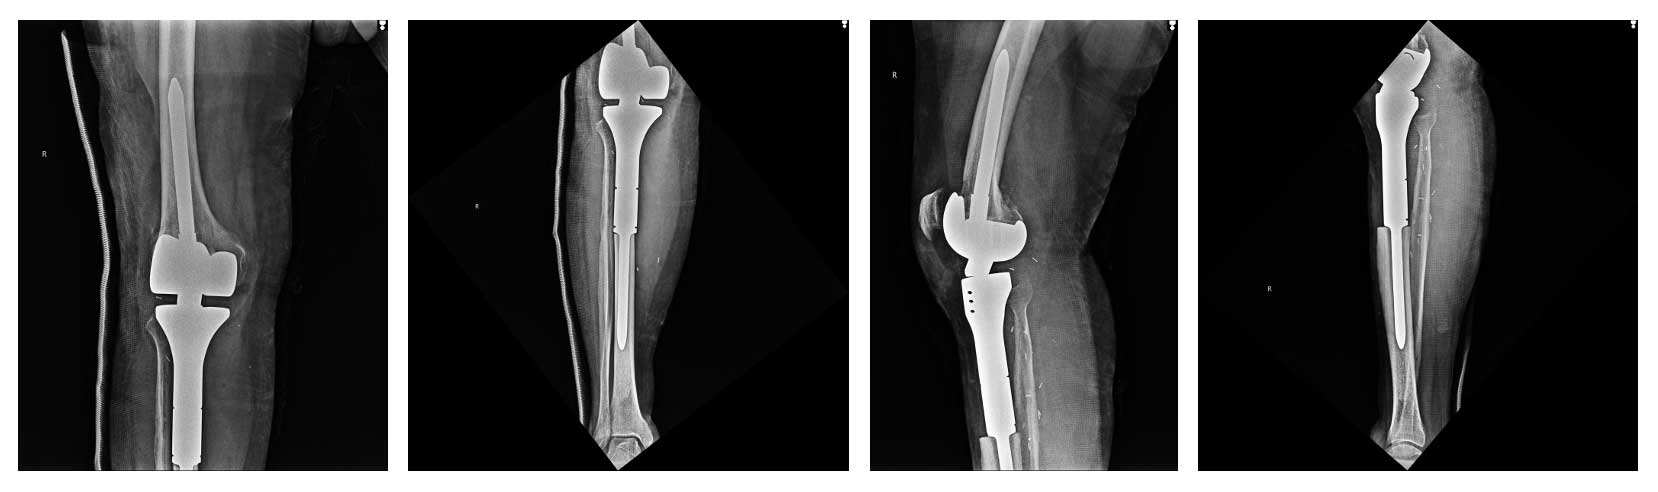

Hastaya kemoterapi sonrasında geniş rezeksiyon uygulandı. Tümörlü kemik çıkarıldıktan sonra diz eklemi ve çevre dokuların bütünlüğü korunacak şekilde tümör protezi ile yeniden yapılandırma (rekonstrüksiyon) yapıldı. Yumuşak doku kapatılması için gastroknemius kas flebi kullanılarak sağlam ve estetik bir doku örtüsü elde edildi.

Ameliyat sonrası dönem sorunsuz geçmiş, hastada diz stabilitesi ve fonksiyonel hareket kabiliyeti korunmuştur. Hasta yara iyileşmesini takiben onkolojik takip ve rehabilitasyon sürecine yönlendirilmiştir.

Ameliyat Sonrası: Röntgende rezeksiyon sonrası uygulanan tümör protezi görülmekte.